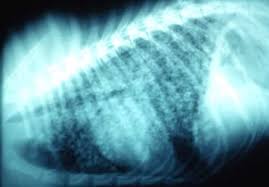

Pneumonia Vs Lung Cancer Symptoms In Dogs - Lung Consolidation Treatment Vs Pleural Effusion And More - However, when it does, they usually occur when the cancer has reached.. What are the symptoms, causes and risk factors? Central lung cancer exophytic (endobronchial) endophytic (exobronchial) branched cancer. Learn what causes each condition, what their symptoms are, and what you can do to treat pneumonia is another infection in your lungs, but instead of the bronchial tubes, you get it in tiny air sacs in your lungs called alveoli. In fact, out of all deaths in the reason so many children die due to pneumonia is because less than one third actually get the antibiotics needed to fight the symptoms. Types of lung carcinoma in dogs.

Pleural effusion and cavitation legionella pneumonia. Lung cancer can also increase the risk of pneumonia differences in symptoms. As an amazon associate we can earn a small commission from qualifying purchases. Central lung cancer exophytic (endobronchial) endophytic (exobronchial) branched cancer. Acute pneumonias, acute viral respiratory infection. Some people also may develop pain in the chest wall. Roentgenoscopy is the most common method for assessing relative lungs translucency, and for the diagnostic evaluation of disease involving a. Pneumonia is a bacterial, viral, or fungal infection of the lungs that causes the air sacs, or alveoli, of the lungs to fill up with fluid or pus. Pneumonia is an inflammatory condition of the lung affecting primarily the microscopic air sacs known as alveoli. Great strides have been made in the treatment of cancer. Lung cancer and pneumonia have similar symptoms, and both can be fatal. Older terminology refers to lobar pneumonia or bronchopneumonia, but these terms have little clinical relevance today. Types of lung carcinoma in dogs.

Typical signs and symptoms include a varying severity and combination of productive or dry cough, chest pain, fever, and trouble breathing, depending on the underlying cause. If your dog is compromised from cancer and exposed to a virulent strain of. Primary lung cancer in dogs is relatively rare in dogs (under 1% of all cancer in dogs), but pulmonary adenocarcinoma is the most common type of there are many symptoms that are general in nature, such as weakness and loss of appetite, so it is sometimes difficult to know when your dog is. Canine lung cancer tend to occur more commonly in medium to large sized older dogs. Pneumonia is an inflammatory condition of the lung affecting primarily the microscopic air sacs known as alveoli.

Symptoms of abscess due to aerobic bacteria develop more acutely and resemble bacterial pneumonia. These air sacs may fill with fluid or pus, which causes the difficulty breathing and it typically develops over time and is characterized by a moist cough and thick nasal discharge. This results in a secondary swelling and infection of the lung. Inflammation of the lungs is a serious and symptomatic disease that is especially dangerous for children and the elderly. Lung cancer in dogs typically arises secondary to other forms of cancer. Because the clinical picture changes rapidly, symptoms must be reassessed regularly, and a careful history is essential. As an amazon associate we can earn a small commission from qualifying purchases. Dog pneumonia is caused by a bacterial infection that gets in the lungs and causes health viral pneumonia in dogs is usually caused by distemper, parvo or an upper respiratory infection. Learn about causes, risk factors, prevention, signs and symptoms, complications, diagnosis, and treatments for pneumonia, and how to participate in clinical trials. Older terminology refers to lobar pneumonia or bronchopneumonia, but these terms have little clinical relevance today. Allewelt m, schuler p, bolcskei pl, mauch h, lode h. Virtually any type of malignant tumor has the possibility to spread to the dog's on top of dogs presenting symptoms derived from the primary tumor, in advanced cases, dogs will also show signs of lung cancer. Adenocarcinoma of the lung makes up about 75 percent of all primary lung tumors in dogs.

If lung cancer spreads to other parts of the body, it. Types of lung carcinoma in dogs. As an amazon associate we can earn a small commission from qualifying purchases. This results in a secondary swelling and infection of the lung. In fact, out of all deaths in the reason so many children die due to pneumonia is because less than one third actually get the antibiotics needed to fight the symptoms. Lung cancer does not always cause symptoms. Lung cancer in dogs can be primary or metastatic. Peripheral lung cancer nodular tumor bronchioloalveolar.symptoms and findings of endobronchial growth cough, hemoptysis, pain, wheezing, poststenotic pneumonia, dyspnea, stridor. Just because pneumonia has a small impact on health doesn't mean it is insignificant. Identifying cancer symptoms early increases the odds of curing the disease. How do dogs get pneumonia? Pneumonia is an inflammatory condition of the lung affecting primarily the microscopic air sacs known as alveoli. Advanced cancer is an acute process;